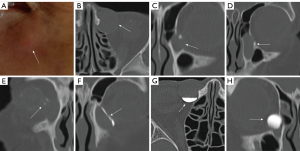

Periorbital swelling, indicated by the elevation of the skin on the LSC side by 1.52±0.64 mm above the surface, was observed and considered a suggestive sign (Figure 1A and Table 1). The CT scans of the LSC showed round or oval-shaped cystic low-density masses originating from the lacrimal sac (Figure 1B). The mean diameters of the lacrimal sac in the axial, coronal, and sagittal planes were 10.79±2.59, 12.84±3.68, and 12.02±3.45 mm, respectively (Table 1). The mean maximum cross-sectional area in the axial plane was 107.24±47.37 mm2 (Table 1). The average distances from the MTA to the upper and lower limits of the LSF were 3.34±3.37 and 11.00±4.40 mm, respectively. Most LSCs (53.33%) were confined to the level of the lacrimal sac (Figure 1C and Table 1), while 46.67% involved the superior intraosseous segment of NLD (Figure 1D and Table 1). Of the patients, 93.33% showed significant contrast interruption in the naso-LDS, indicating NLD obstruction, while 6.67% had patent NLD. Superior NLD obstruction was observed in 40.00% of the patients, middle and inferior NLD obstruction was observed in 43.33%, and common canalicular obstruction was observed in 26.67% (Table 1).

CT-DCG imaging revealed four primary patterns. First, following the injection of contrast agent into the lacrimal duct, 26.67% of the LSC patients exhibited contrast agent blockage in the common canaliculus, and no or weak visualization of the contrast agent in the lacrimal sac and NLD (Figure 1E and Table 1). Second, 46.67% of the LSC patients showed enhancement of the cyst wall, characterized by a thin rim of enhancement (Figure 1F and Table 1). Third, a pattern of contrast agent accumulation, termed the “fluid level,” was observed at the base of the cyst (Figure 1G), and 50% of the LSC patients exhibited a discernible fluid level with smooth margins in both horizontal and sagittal planes (Table 1). Fourth, 20% of the LSC patients exhibited a conspicuously cystic lumen with a fluid-filled “lightbulb” sign (Figure 1H and Table 1), ruling out a solid tumor.